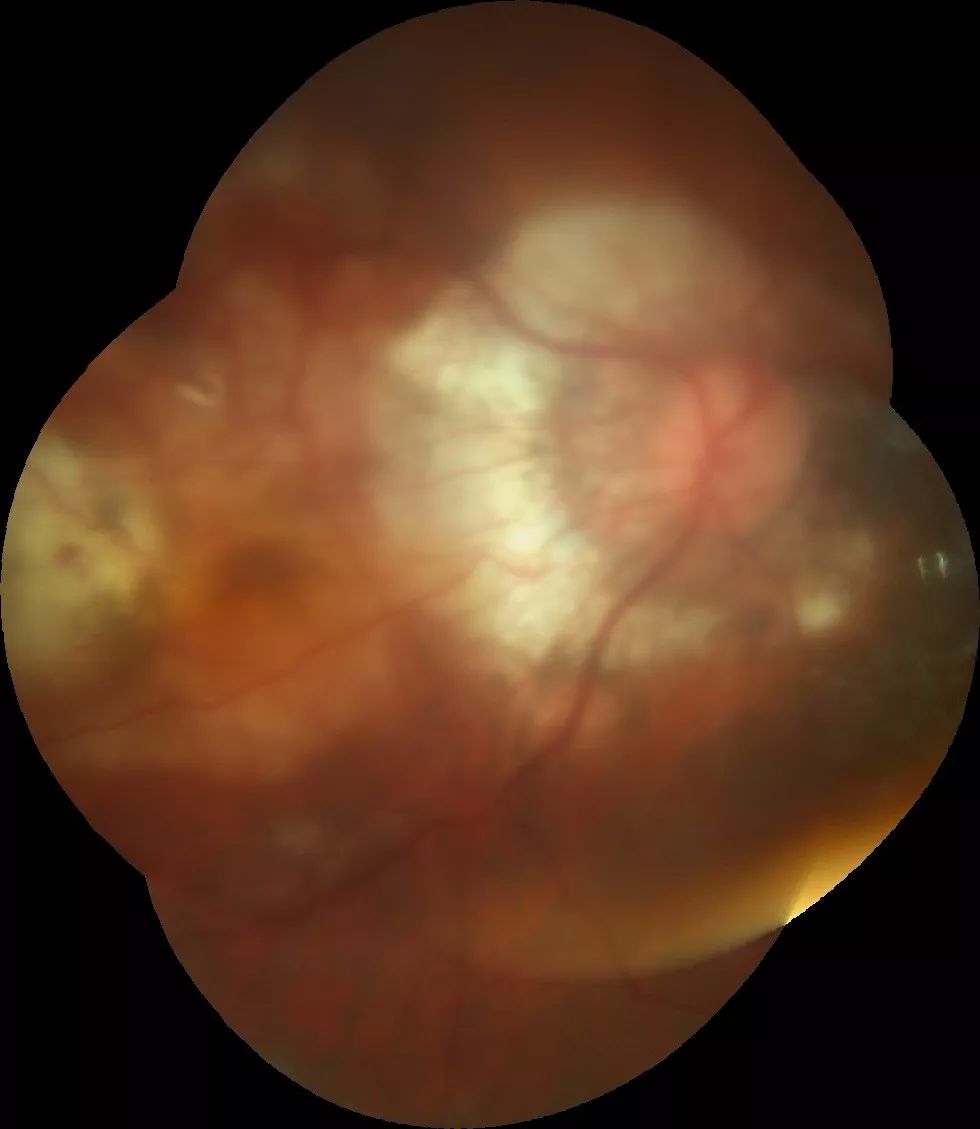

2月9日,刘清云主任又为一位视网膜脉络膜脱离的患者实施了手术,这是一例非常复杂的玻璃体手术,患者视网膜脉络膜几乎全周脱离,手术后患者的视网膜脉络膜全部复位,患者高高兴兴的出院回家过年了,出院前患者家属握着刘主任的手感激不已。如此高难度的手术,即使在北京那些大医院也只有少数医生可以顺利完成,但是对于刘清云主任来说,这样的手术已经是常规。